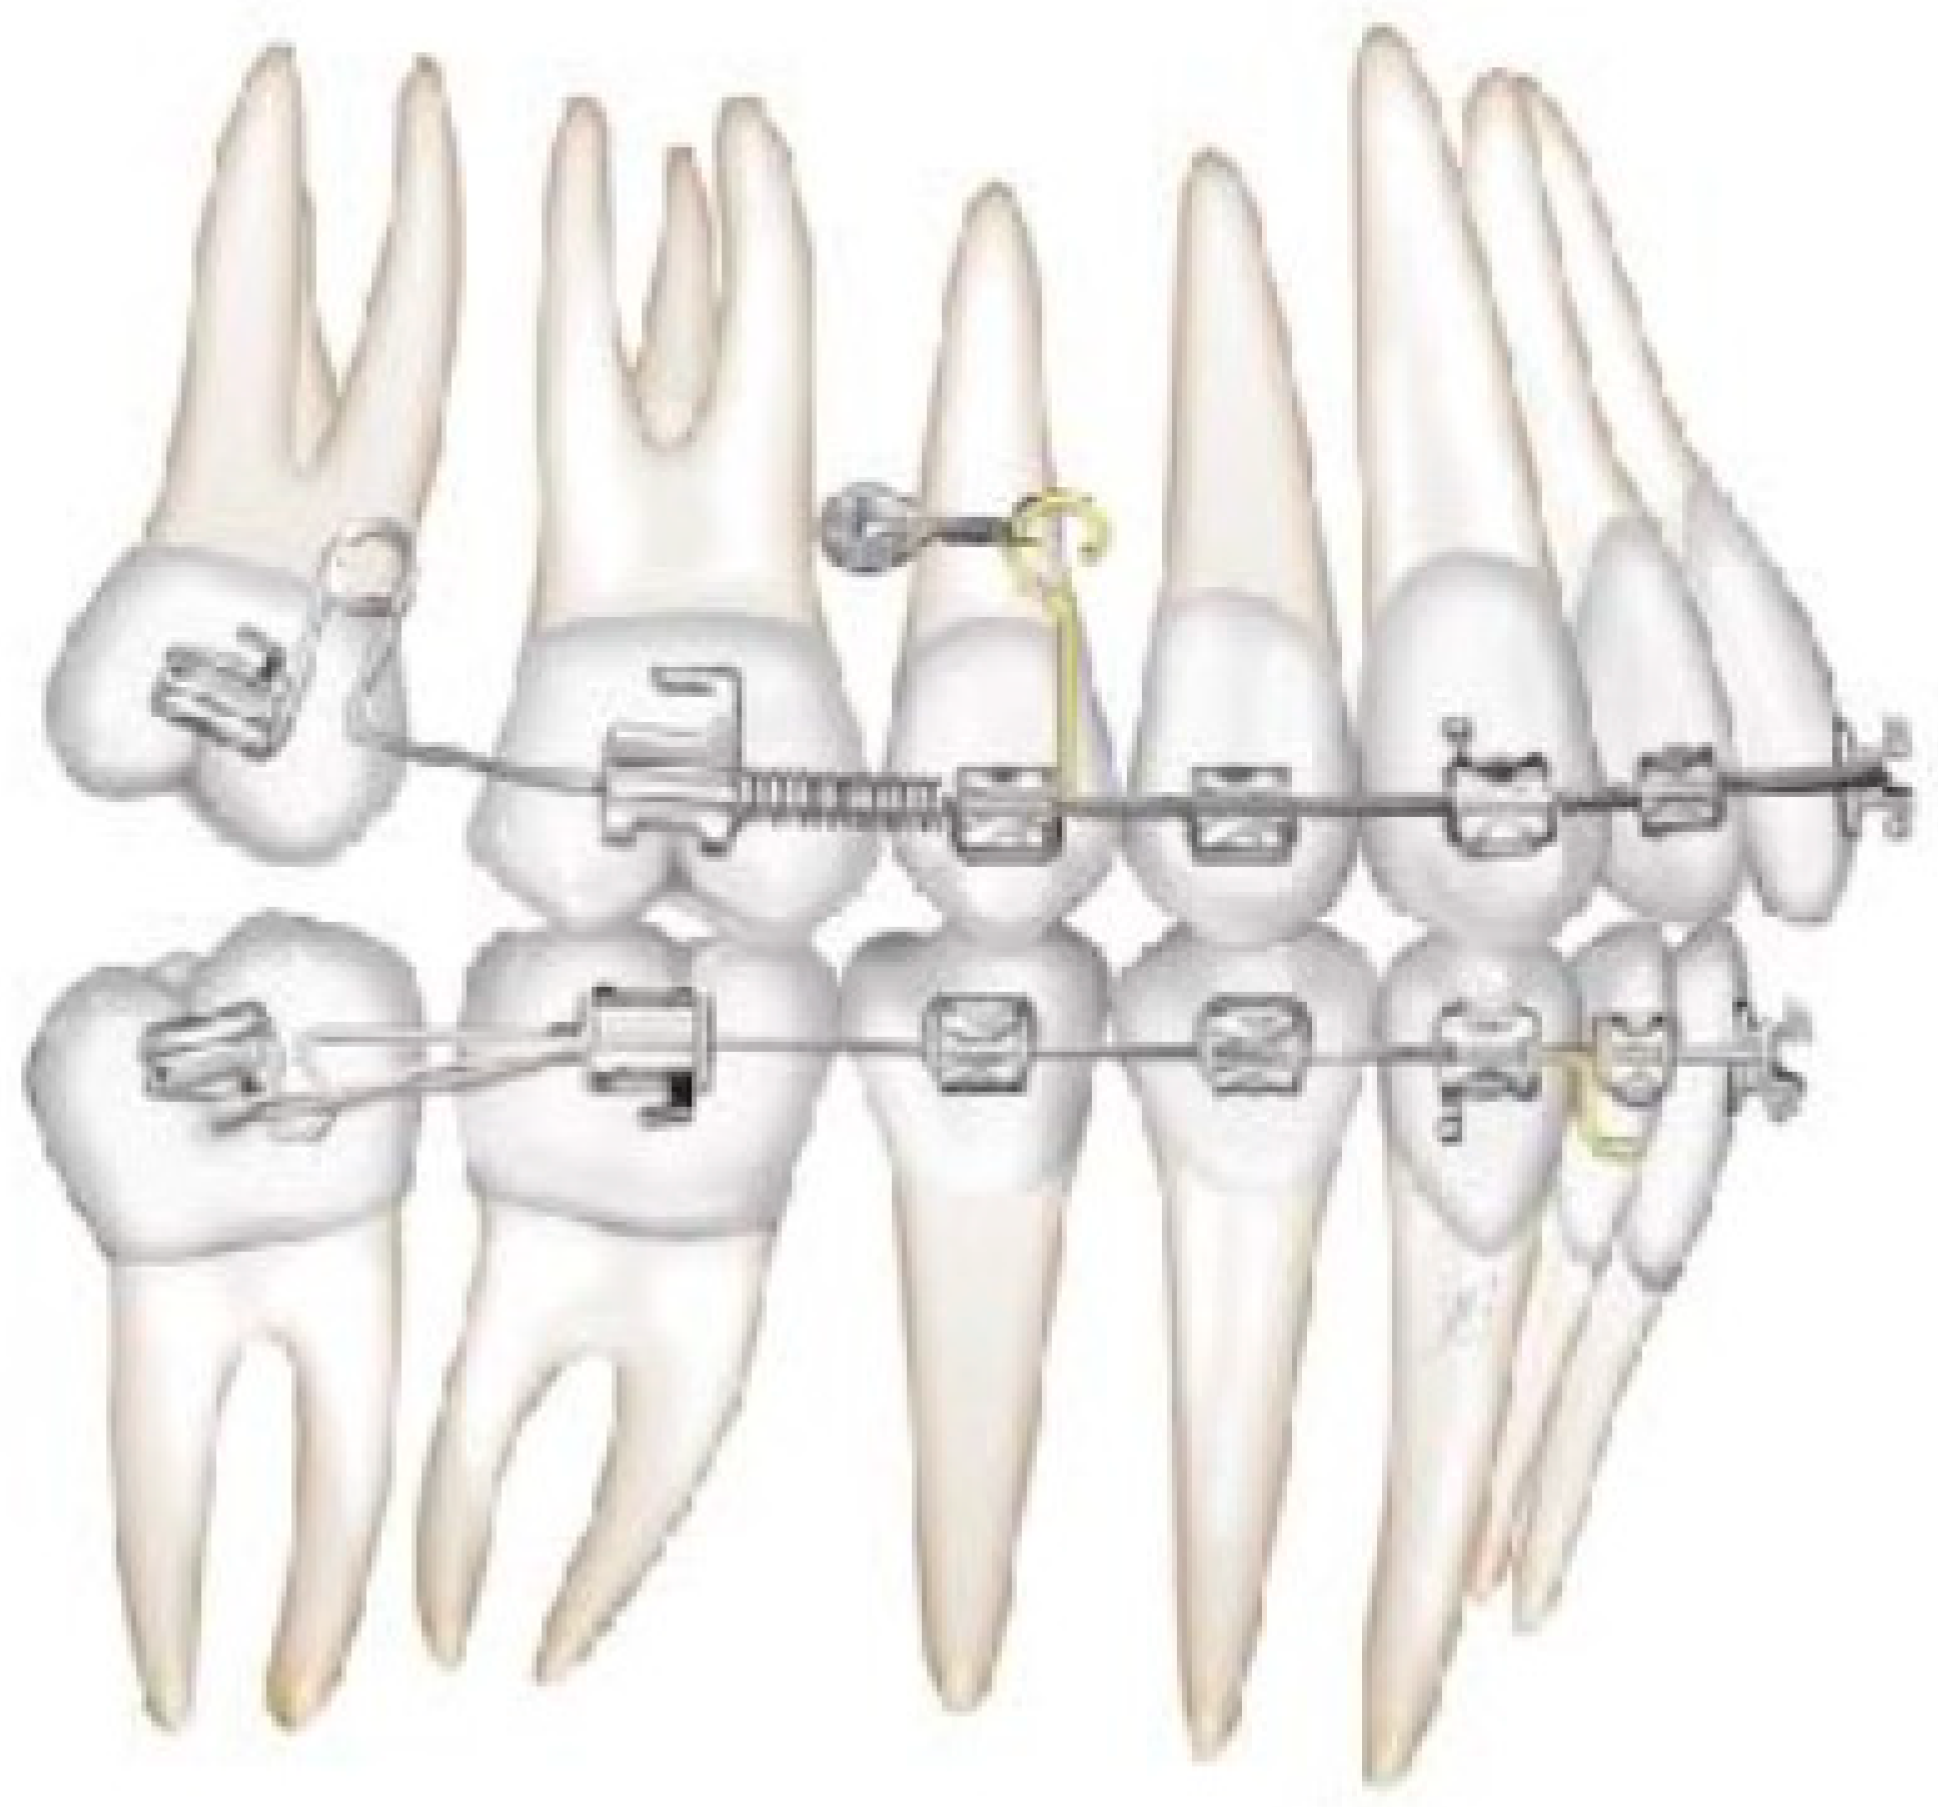

2.3. Canine and Incisor Distalization

In this case, right after the spontaneous eruption, a power chain from the right tad was used to derotate and distalize the right upper canine (Figure 8). On the upper arch, a 0.20 × 0.25 SS wire was prepared with modified “cactus-shaped” closing loops, with the aim to close the space between the canines and the laterals. The cactus loop has a double aim. First of all, it is used as a closing loop; activation is produced by tying the loop through a metallic ligature from the tads. Secondly, it serves as a hook for cantilevers. The cantilevers are made using 0.19 × 0.25 TMA. The retraction of the upper incisors is supported by two cantilevers applied distally on the tads. The cantilevers will support the mechanics in order to produce intrusion of the incisors and torque control during retraction [1] (Figure 9 and Figure 10).

Figure 9. Canine and incisor distalization strategy: The cantilevers produce intrusion of the incisors and torque control during retraction.

Figure 10. Canine and incisor distalization strategy.